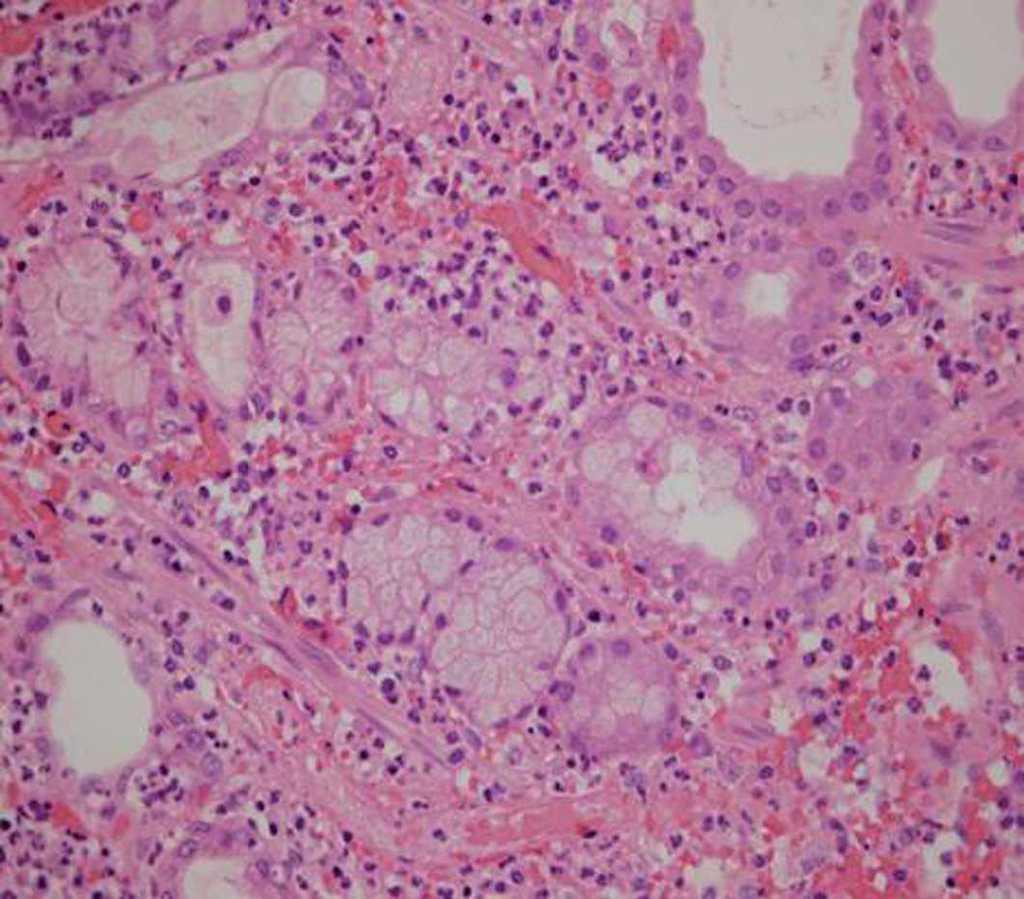

La anatomía patológica constató divertículo de Meckel con metaplasia de mucosa duodenal en la pared de éste; se observaron escasas glándulas de Brunner y algunas células de Paneth (fig. 2). En la formación diverticular se evidenciaron signos de necrosis isquémica que afectaban a mucosa y sub-mucosa, junto con pared hemorrágica y denudación de todo el epitelio. Se objetivó obliteración fibroadiposa de la luz en la punta apendicular.

Fig. 2 – Imagen microscópica de la mucosa duodenal.